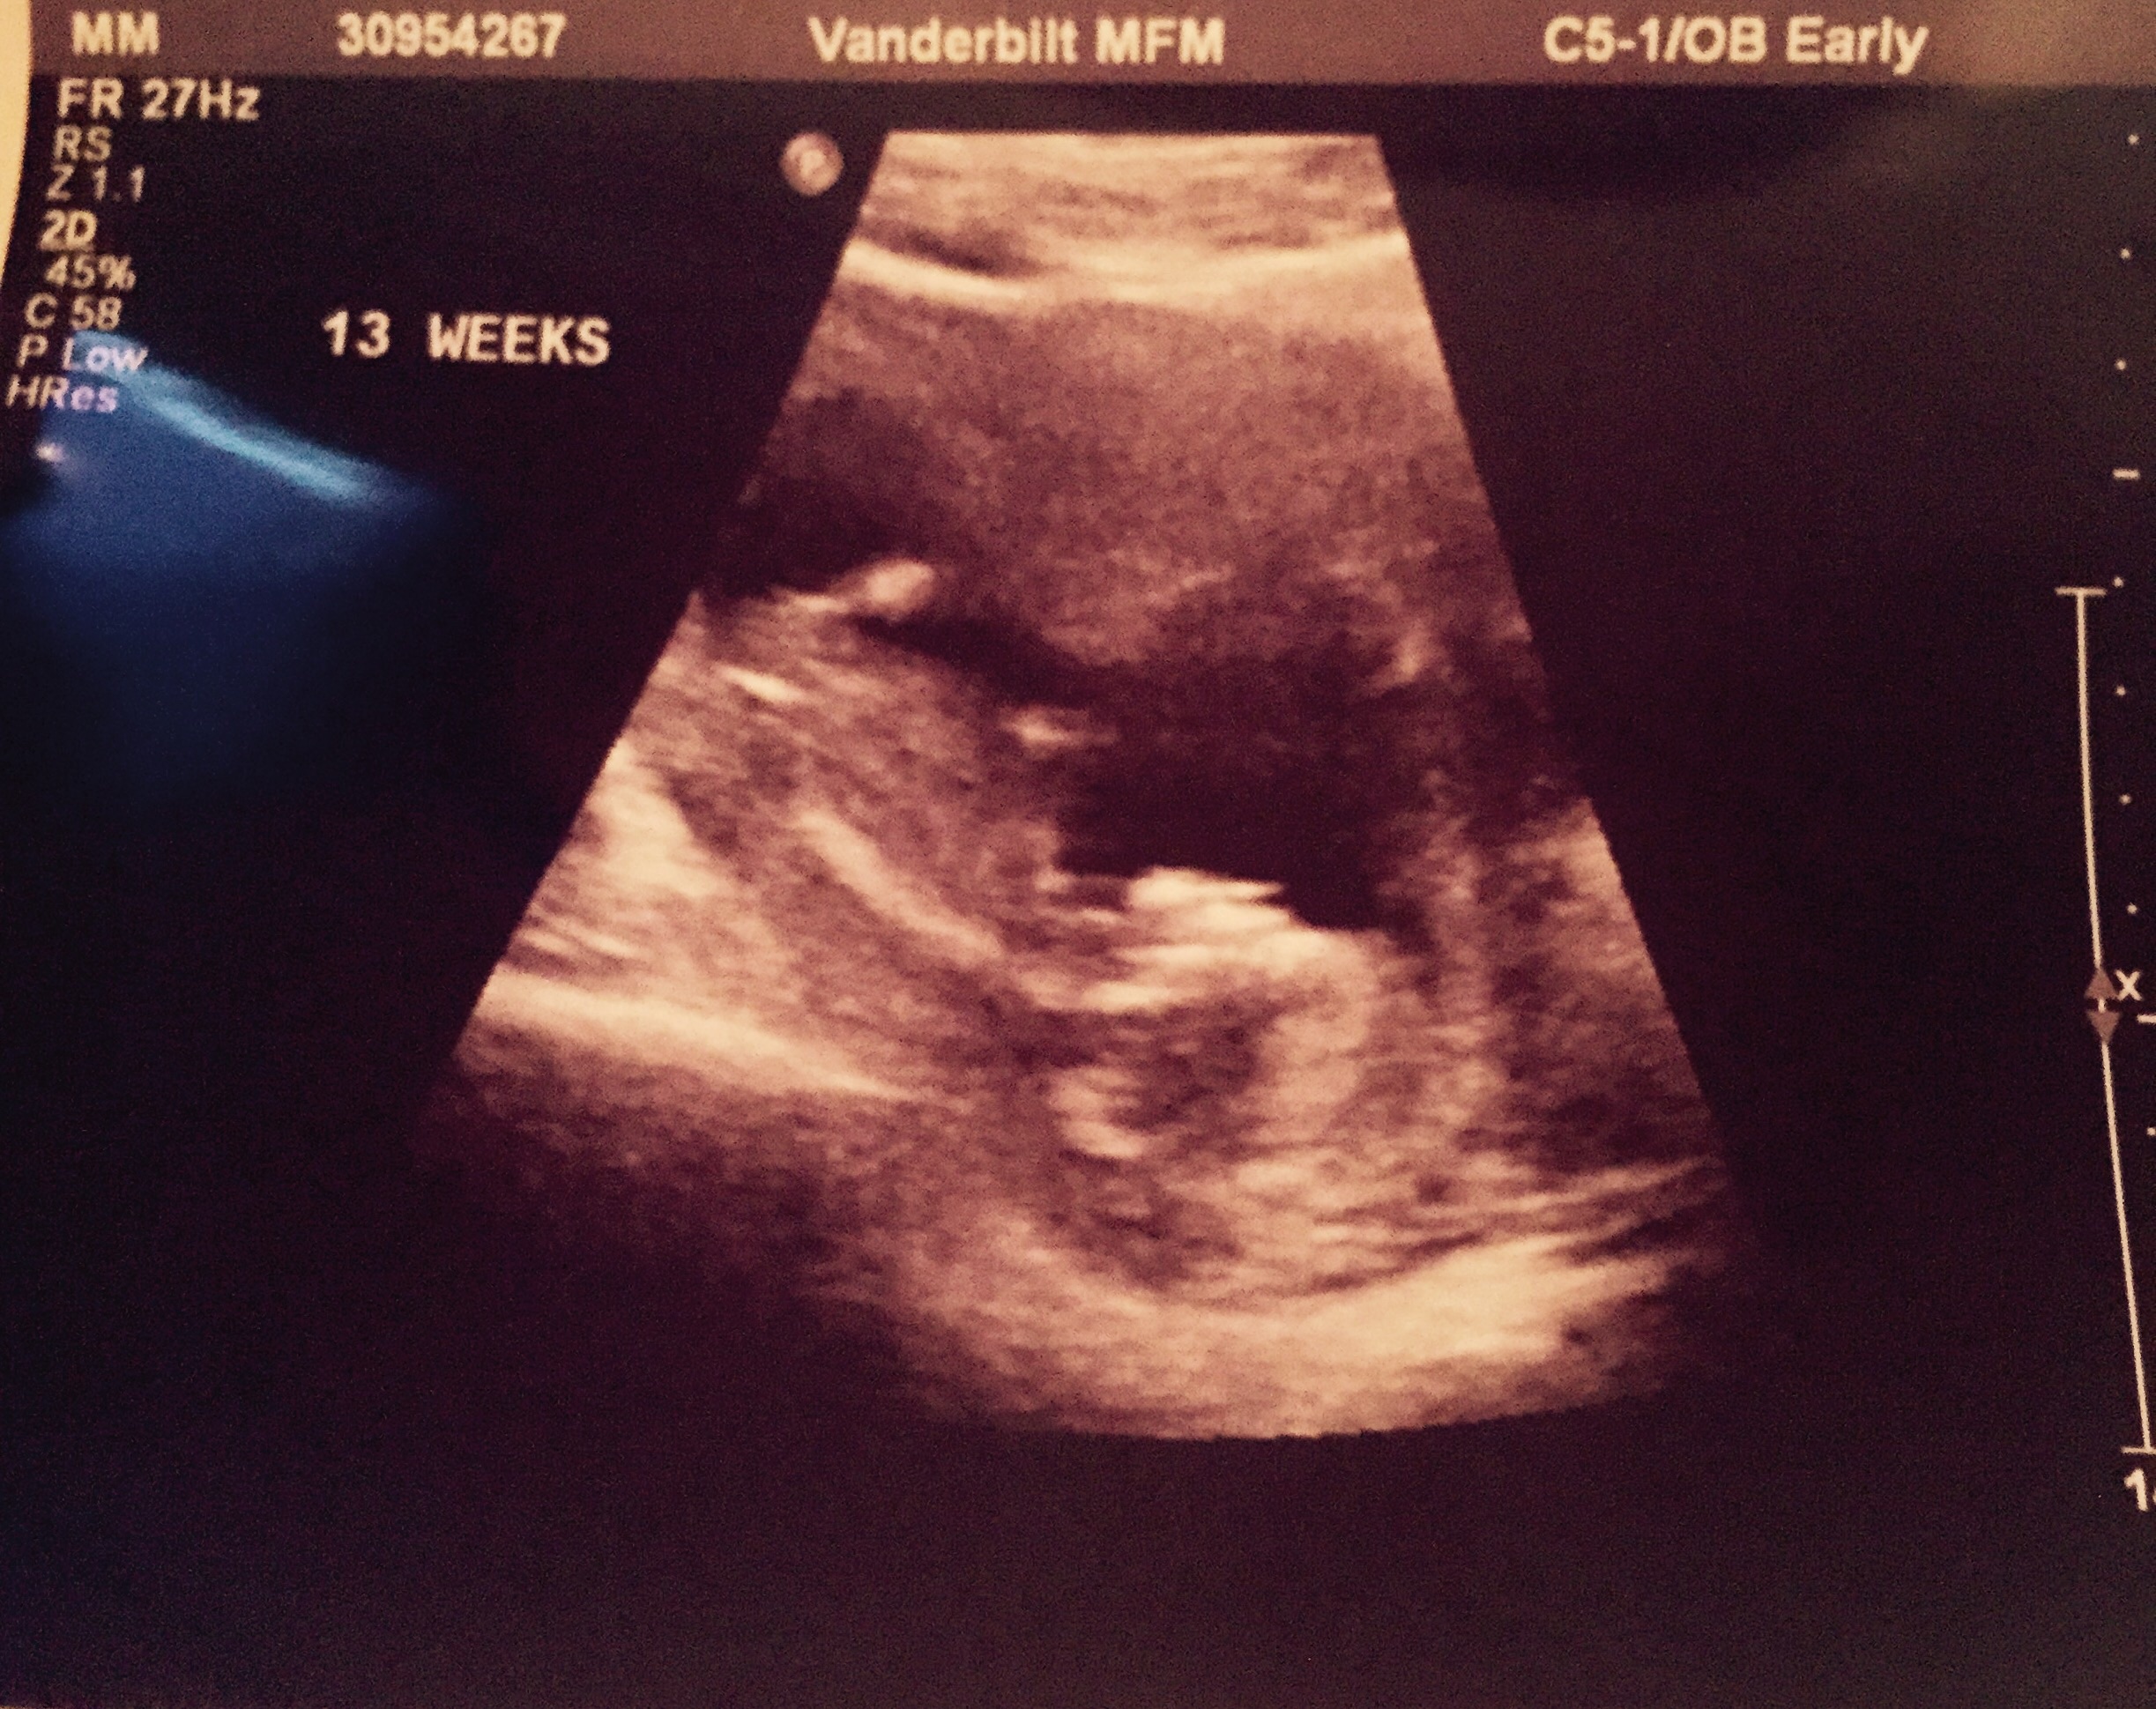

We had our 13w1d ultrasound appointment today. It was much longer than our 7week appointment and I loved every second of it. I could not believe how wiggly my little peach was. The heart beat was steady and strong. My mind is blown every time I look at the pics or watch the snippet of video we took. In love!